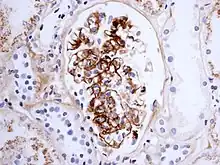

紫癜处皮肤活检可见IgA沉积于血管壁,并见白细胞破裂性血管炎。

肾小球的毛细血管炎可引起急性肾炎综合征,严重者可出现新月体形成;还有少数病例反复发作,迁延为慢性肾炎综合征或肾病综合征。